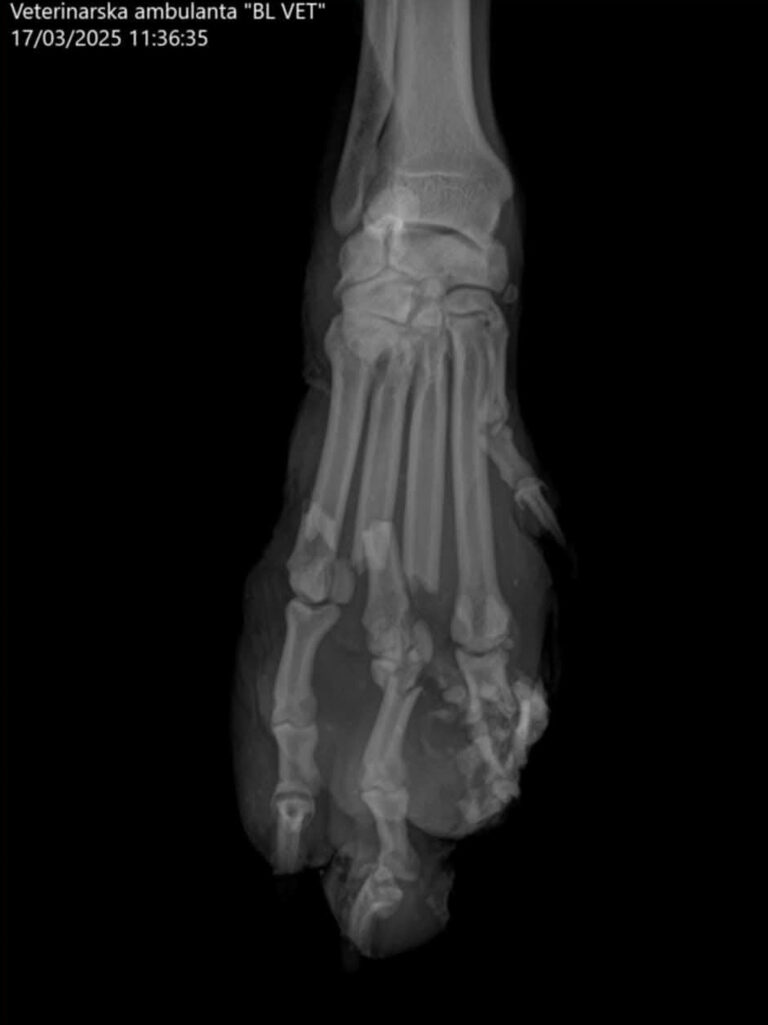

Bark war ein bosnischer Streuner, der von der ganzen Nachbarschaft geduldet und sogar gefüttert wurde. Dann kam er eines Tages so an die Tür. Niemand weiß, was passiert ist, aber da die Bahn gleich gegenüber ist, denken wir, dass er von einem Zug erfasst und schwer verletzt wurde. Die grausamsten Bilder ersparen wir euch. 😮‍💨